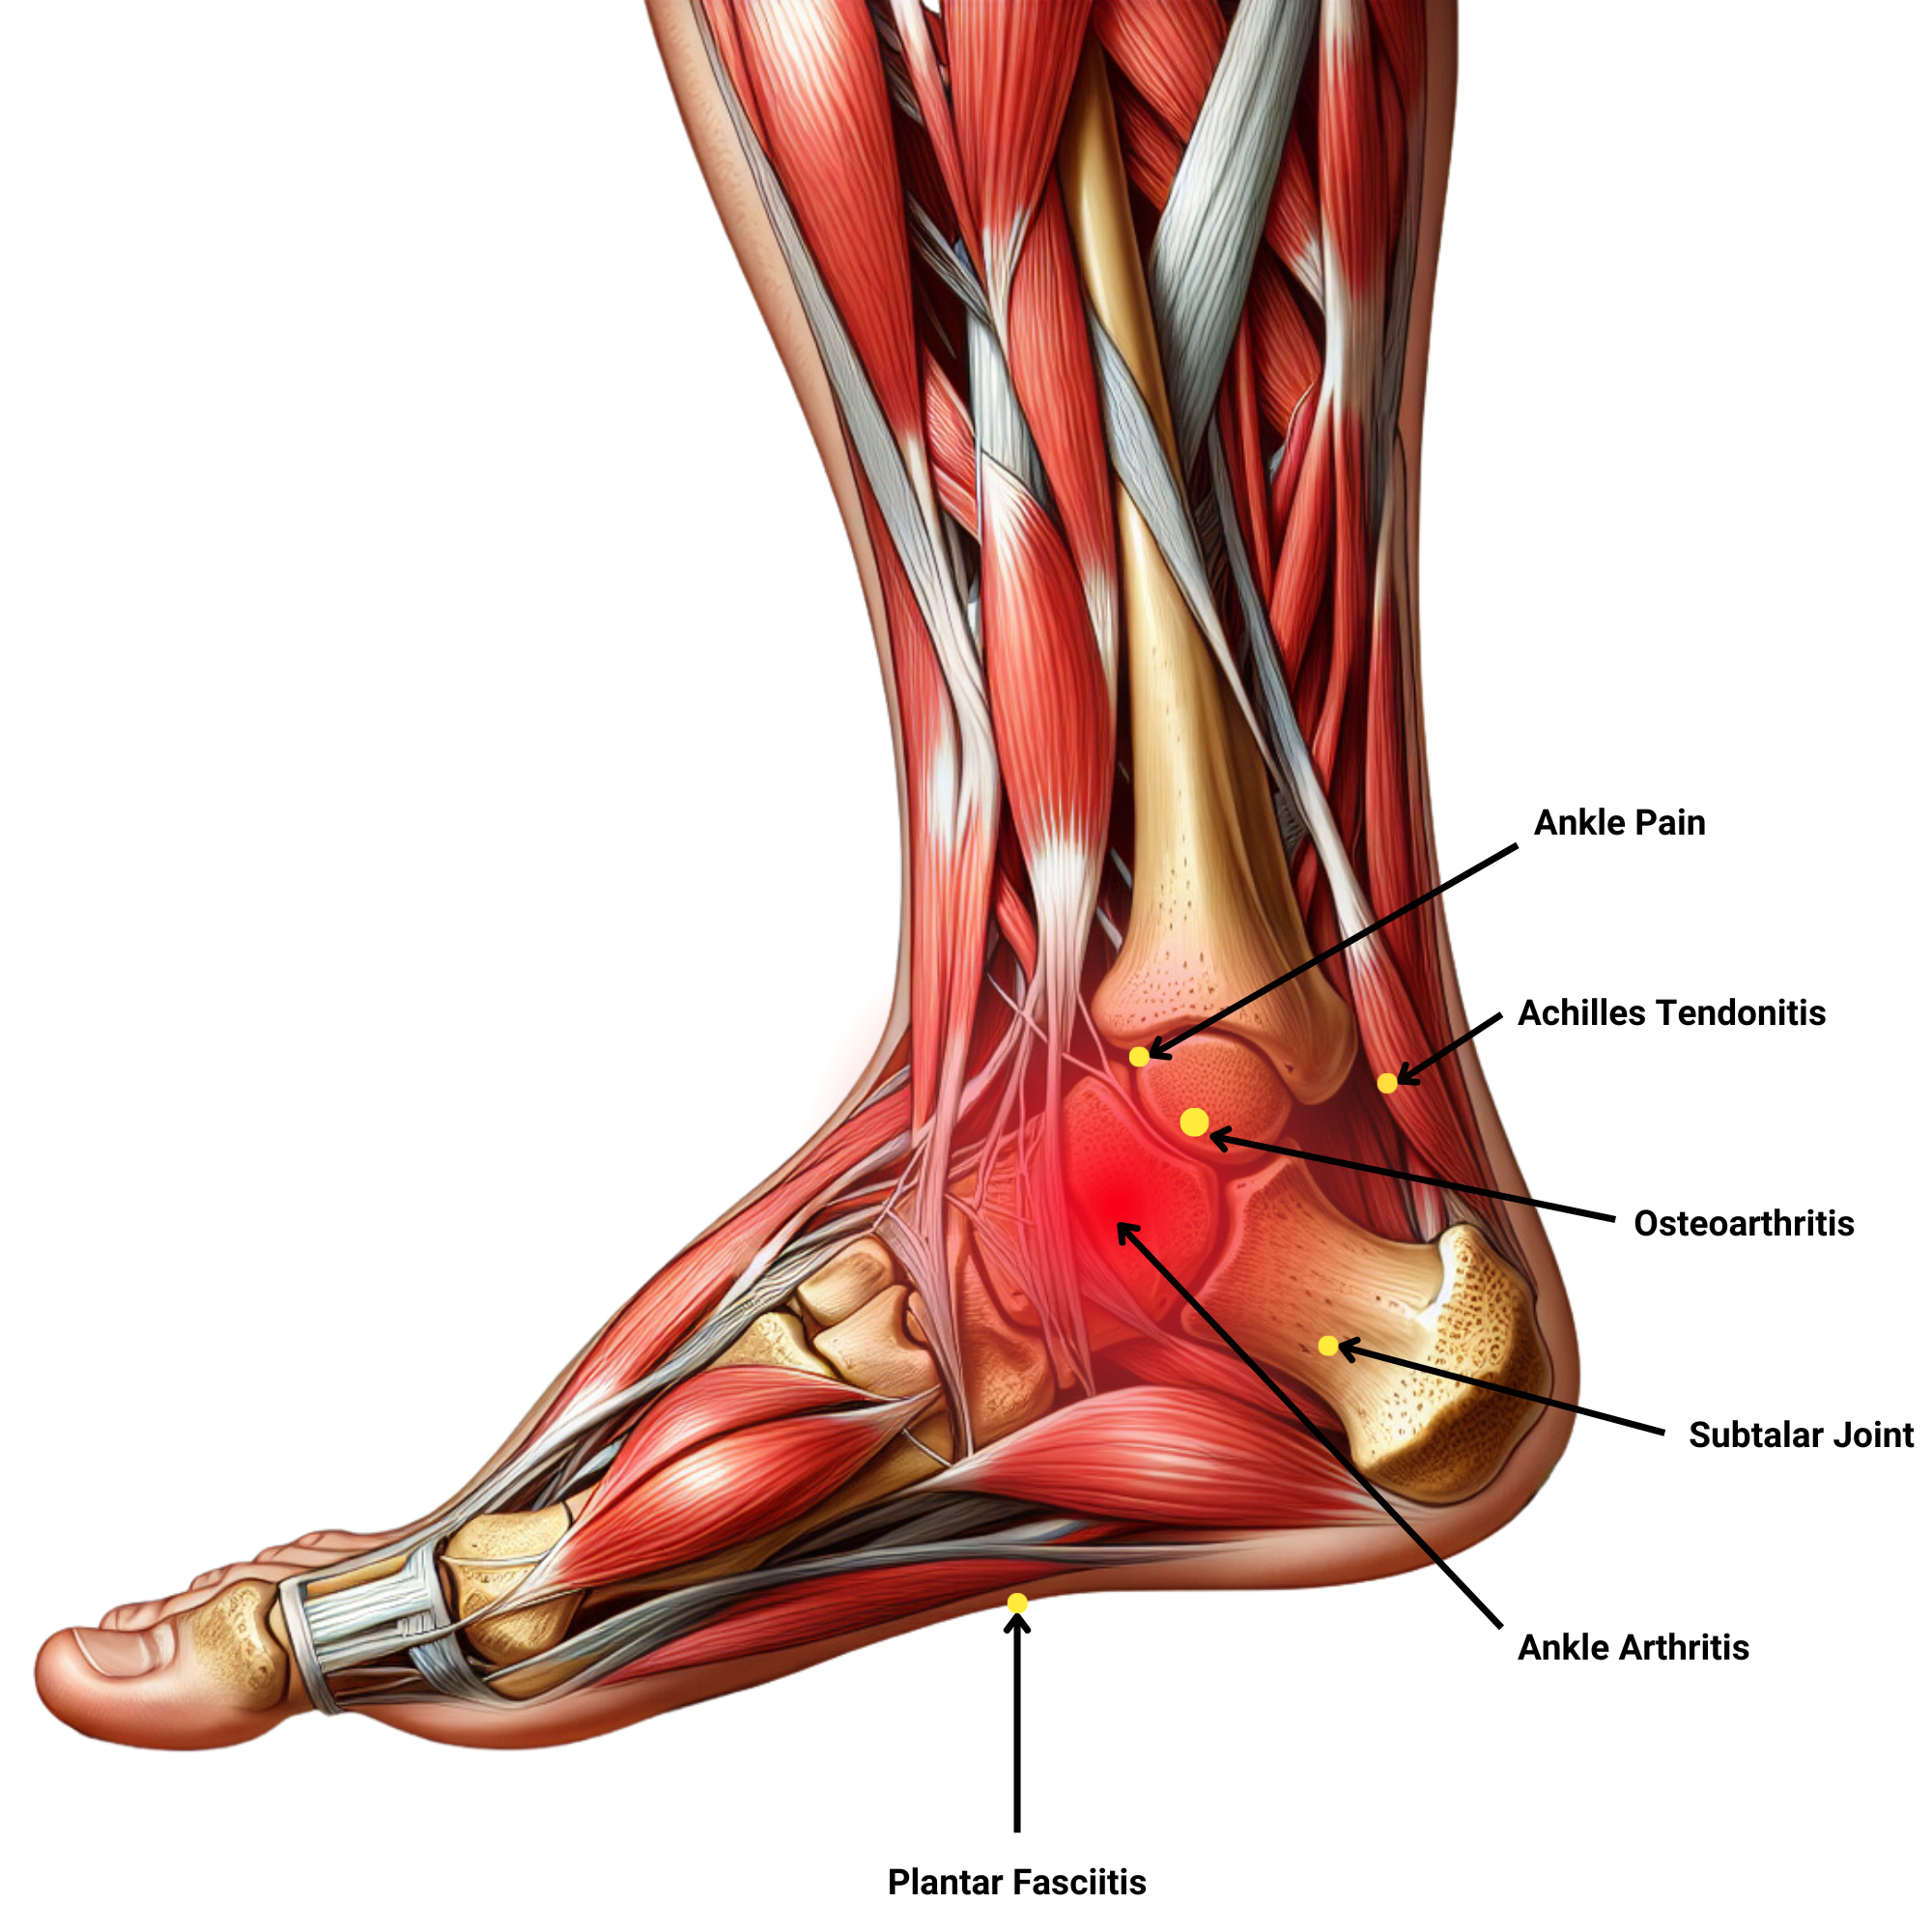

Feet and Ankles

The foot and ankle are complex parts of the body that comprise 26 bones and 33 small joints that are supported by muscles, tendons, ligaments, blood vessels, and nerves. It is common to experience pain and mobility issues around the feet and ankles at some point in your life.

The feet and ankle are supposed to naturally move in more than one direction, and therefore, linear movement patterns restrict the ankle’s range of motion.

Our movement program will improve functional performance of the feet and ankles, and address issues in the areas shown in the image above, with the following outcomes:

- Reduce tightness and excessive load

- Alleviate pain and inflammation

- Strengthen supporting muscles

- Restore the joint’s range of motion

- Enhance joint stability

- Increase blood circulation

- Boost synovial fluid circulation

- Improve proprioception and balance

- Relearn proper foot mechanics

- Address compensatory patterns